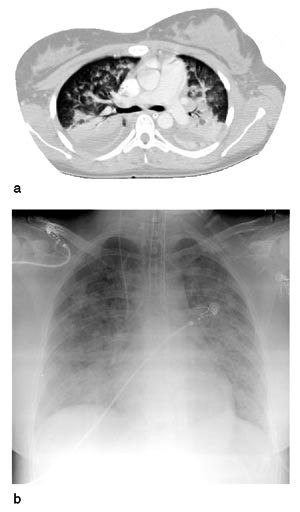

Røntgen thorax og CT thorax med lungeemboliprotokoll var normale. Ekkokardiografi ble gjort med tanke på mulig aortadisseksjon, men undersøkelsen viste normale forhold. CT abdomen viste kun litt ødem rundt galleblæren samt litt væske i abdomen. Gynekologisk undersøkelse var normal. EKG viste uspesifikke ST-segmentforandringer. Blodprøver viste pO₂(a) 8,9 kPa, pCO₂(a) 5,1 kPa, pH 7,37, aktuell bikarbonat 21,5 mmol/l, baseoverskudd –3,4 mmol/l, CRP 11 mg/l, pancreasamylase 770 U/l (referanseområde 20 – 100 U/l) (fig 1), troponin T 0,7 &181;g/l, CK 157 U/l og CK-MB 21 U/l. Øvrige blodprøver var normale. Serologiske tester for HIV og Legionella samt immunologiske prøver inkludert antinukleære antistoffer (ANA) var negative. Direkte mikroskopi og undersøkelse med polymerasekjedereaksjon gav ikke holdepunkt for tuberkulose. Dag 3 fikk pasienten kvalme og økende abdominalsmerter. Hun satt fremoverlent i sengen med flekterte knær og ble økende dyspneisk og takypneisk med frekvens på 50/min. pO₂(a) sank til 7,9 kPa til tross for oksygentilførsel. Hun ble sedert og tilkoblet respirator, og ventrikkelsonde ble nedlagt. Røntgen thorax viste nytilkomne bilaterale, diffuse, flekkvise fortetninger (fig 2). Temperaturen var nå 39,5  °C. Blodprøver viste pancreasamylasestigning til 1400 U/l. CRP var 20 mg/l og albumin 24 g/l. Tilstanden ble oppfattet som akutt pankreatitt med lungekomplikasjoner forenlig med sjokklunge.

Dag 4 tilkom utbredte bilaterale fortetninger forenlig med ødem/eksudat også på CT thorax (fig 2). CT abdomen ble gjentatt, men viste uendrede funn med fortsatt normalt utseende pancreas (fig 3). For å utelukke andre patologiske forhold ble pasienten laparoskopert med normale funn i abdomen og bekken. Hun var nå afebril og det ble ikke påvist vekst av mikrober verken i blod, abdominalvæske eller trakeal-/cervixsekret. Amfetamin, kokain og cannabinoider ble ikke påvist verken i urin eller blod.

Kvinnen var preget av betydelige lungekomplikasjoner med utvikling av bilaterale diffuse fortetninger, dyspné, takypné og hypoksemi som krevde respiratorbehandling. Dessuten forelå tegn på organsvikt uttrykt ved hypotensjon. Lungeaffeksjon er beskrevet som en hyppig komplikasjon til akutt alvorlig pankreatitt og varierer fra mild hypoksemi, atelektase eller pleuraeffusjon via akutt lungeskade til sjokklunge (6). Sjokklunge er sjelden i forløpet av mild pankreatitt. Ved alvorlig pankreatitt er forekomsten av akutt lungeskade/sjokklunge imidlertid 25 – 50 %, og sjokklunge forårsaker over halvparten av dødsfallene i tidlig fase av pankreatitt (7).